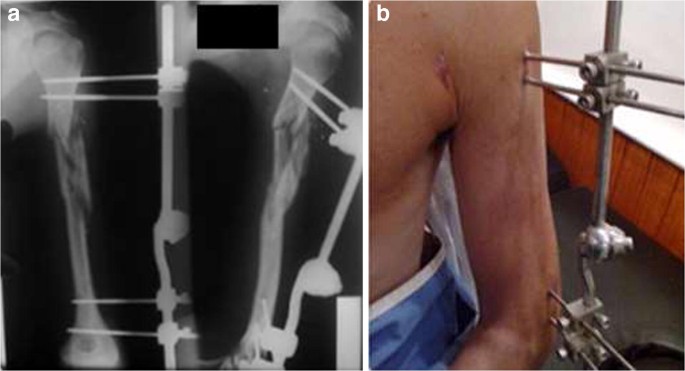

External Fixation involves placing metal pins or screws into the bone fragments on either side of a fracture, which are then connected to an external frame outside the body. This frame holds the bones in the correct position, ensuring stability as they heal.

• Pin Placement: Pins or screws are inserted through the skin into the bone on either side of the fracture.

• Frame Attachment: The pins are connected to a stabilising frame outside the body, which holds the bone fragments in alignment.

• Adjustment Capabilities: Many external frames can be adjusted to correct alignment as healing progresses.